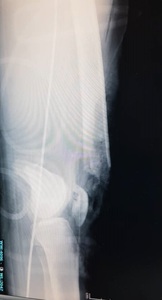

A 22-year-old man presented to our hospital in December 2020 following a motor vehicle accident. The patient had no significant medical, family, or allergy history. He worked in a metal factory and occasionally smoked. The sustained injuries included a closed fracture of the right neck of the femur, an open right supracondylar femur fracture (Gustilo 3C), and an open midshaft fracture of the right tibia (Gustilo 2) (Figures 1, 2, and 3).

Initial management involved screw fixation of the femoral neck, wound debridement of the right thigh, and placement of an external fixator across the right knee (Figures 4 and 5), followed by a one-week course of intravenous cefuroxime. By January 2021, the right leg had become gangrenous and deemed nonviable. Right above-knee amputation (AKA) with adductor myodesis was performed, followed by intravenous cefuroxime for another week.